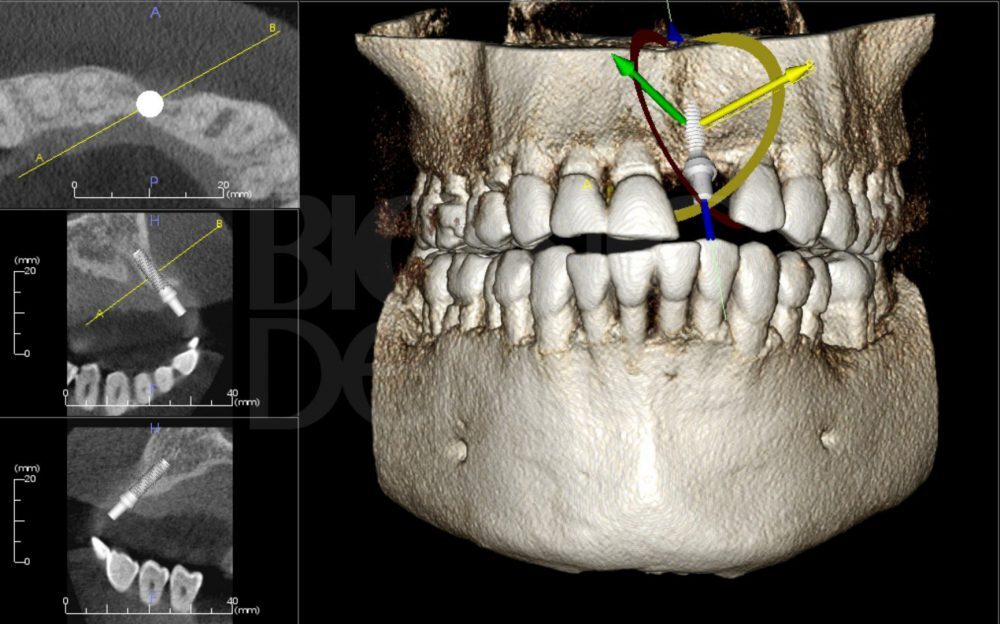

3D-снимок зубов. Трехмерный снимок зубов создается с помощью обновленного ортопантомографа, оснащенного современнейшим программным обеспечением, которое используется для обработки получаемых данных. Этот вариант компьютерной томографии оказывает намного меньшую лучевую нагрузку на организм пациента и может использоваться как на раннем этапе диагностики, так и во время лечения зубов.

Компьютерная томография. Дентальная КТ используется для получения снимка зубов в нескольких плоскостях и с разной глубиной сканирования. Преимуществом компьютерной томографии является отсутствие искажений на полученном снимке. В отличие от пленочного рентген-аппарата томограф не оказывает сильной лучевой нагрузки на ткани, поэтому разрешен даже для исследования зубов беременных женщин и детей.